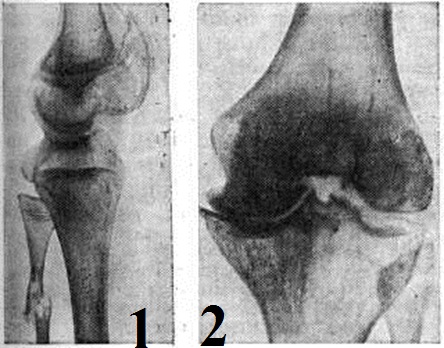

При Гемофилия лёгкой и средней тяжести осложнения возникают редко. Повторные кровоизлияния в сустав вызывают утолщение капсулы, узурирование хряща и остеопороз. При кровоизлияниях в коленный сустав, который поражается чаще, кровь скапливается в верхнем завороте, вызывая резкие боли и вторичную рефлекторную атрофию четырёхглавой мышцы. При отсутствии лечения развивается стойкая контрактура. Характерно образование кровяных кист в метафизе, реже в диафизе трубчатых костей. Иногда кисты локализуются в тазовых, пяточных костях. Наличие деструктивных процессов в костях нередко приводит к патологический переломам (рисунок 1). При обширных подкожных, внутримышечных, забрюшинных кровотечениях может наступить сдавление сосудов и нервов с последующим развитием некрозов, параличей и ишемической контрактуры.

Рис. 1. Рентгенограмма нижней трети бедра и верхней трети голени больного гемофилией. Патологический перелом малоберцовой кости в области кисты.

Рис. 2. Рентгенограмма коленного сустава при гемофилическом остеопорозе (III стадия): резкое сужение медиальной части суставной щели, костные разрастания по краям.

Рентгенодиагностика изменений костей и: суставов характеризуется признаками поражения опорно-двигательного аппарата вследствие кровоизлияний в полости суставов, в костномозговые пространства и в мягкие ткани.

Однократные кровоизлияния в суставы могут быстро и бесследно рассасываться. В острый период гемартроза рентгенологическое. Картина не специфична. На рентгенограммах иногда обнаруживается небольшое расширение суставной щели, обусловленное скоплением крови.

Повторные кровоизлияния в суставы приводят к гемофилическому остеоартрозу. Рентгенологическим признаком повторных кровоизлияний, начавшихся в детском возрасте, является изменение размеров и формы сустава.

Рентгенологически различают четыре стадии гемофилического остеоартроза. На рентгенограммах в I стадии обнаруживают остеопороз суставных концов и утолщение суставной капсулы. II стадия характеризуется уменьшением объёма движений в суставе за счёт утолщения капсулы и образования внутри сустава организующихся гематом. В III стадии выявляют сужение суставной щели и изменение конфигурации суставных концов костей вследствие разрушения подхрящевых отделов эпифизов, костных разрастаний (рисунок 2), кистовидной перестройки эпифизов. В IV стадии суставная щель на рентгенограммах не видна или резко сужена. Подхрящевые отделы эпифизов значительно склерозированы.